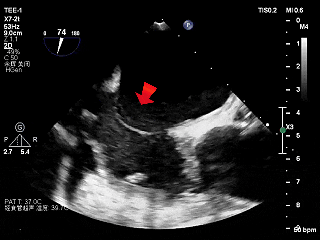

常规经食道超声心动图(TEE)评估发现,左心耳血流速度明显减慢,流速约 24 cm/s,提示存在血栓形成高风险因素,但左心耳内未见自发显影。此外,TEE发现巨大房间隔膨胀瘤(ASA,大小约28×10mm),同时合并卵圆孔未闭(PFO),且ASA腔内可见明显自发性显影(SEC),其内血流速率明显减慢(20.8cm/s)。

巨大房间隔膨胀瘤及自发显影